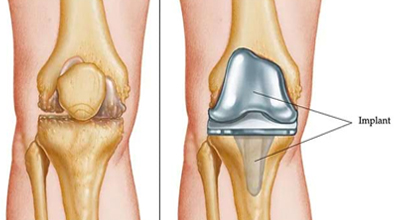

From emergency trauma management to elective procedures like knee replacement, arthroscopy, and spine surgery - our goal is to restore your mobility and improve your quality of life.